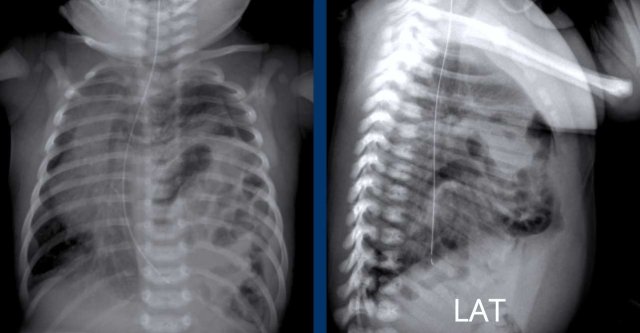

These images are of a neonate gestational age 32 weeks, who was treated for RDS.

Several complications developed, including a pneumothorax on the left side, which was drained.

After drainage there was a deterioration.

Image 1

The radiograph shows bilateral radiating bubbly lucencies due to bilateral PIE.

This is more pronounced on the left side.

Image 2

In follow up the child also developed a pneumothorax on the right side.